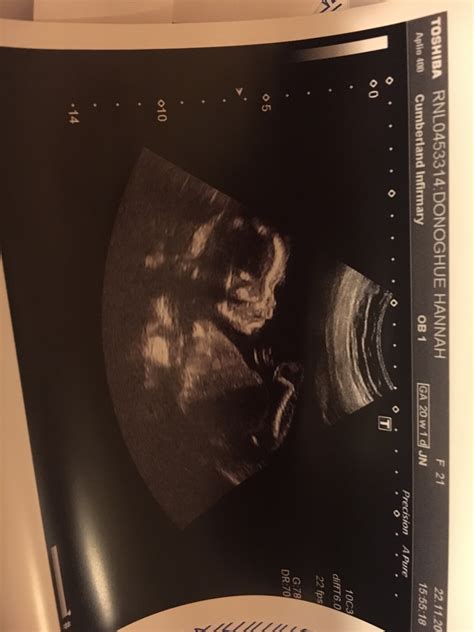

Navigating the world of pregnancy can feel like traversing a minefield of anxieties, especially when it comes to those crucial ultrasound scans. One such scan, the 20-week anatomy scan, is a significant milestone. It’s a detailed check-up, where sonographers meticulously examine your baby’s development. But what happens when this scan brings unexpected news? Discussions around terms like OSCIPSEC and experiences shared on platforms like Reddit can add layers of complexity and, let’s be honest, a fair bit of stress. Let’s dive into what OSCIPSEC might mean in the context of a 20-week scan and how to make sense of information found on Reddit, while keeping a level head.